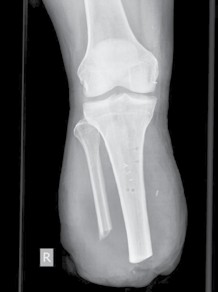

Bei der Amputation versucht man stets, in die Belastungszonen sensible Eigenhaut zu schwenken, die gut unterpolstert ist. Narben sollten nicht in der Belastungszone liegen. Daher ist besonders Haut mit Gefühlsstörungen und/oder solche, die direkt an den Knochen adhärent ist, gefährdet für einen Zusammenbruch ihrer Struktur und die Bildung von Ulzerationen. Diese Schwierigkeiten sind zum Beispiel bei Meshgraft-Transplantaten vorzufinden. So kann es durch Scherkräfte im Prothesenschaft zum Aufreißen transplantierter Haut kommen (Abb. 1). Dennoch sind Meshgraft-Transplantate zur Erhaltung einer maximalen Stumpflänge sinnvoll. Bei jungen Patienten nach traumatischen Amputationen kann die Meshgraft zur Überbrückung eingesetzt werden. In der Interimsphase können sich intakte und dehnbare Haut und Weichteile konditionieren. In einem weiteren Schritt wird die Meshgraft reseziert und der Stumpf vollständig durch Schwenkung von sensibler Haut in die Belastungszone gedeckt. Somit kann für den Patienten eine funktionell sehr wichtige maximale Stumpflänge für die Prothesenversorgung gewonnen werden 3. Ferner darf man nicht vergessen, dass Meshgrafts auf einem belastbaren und gut durchbluteten Muskel sehr gut funktionieren können und keine weitere Revision benötigen.